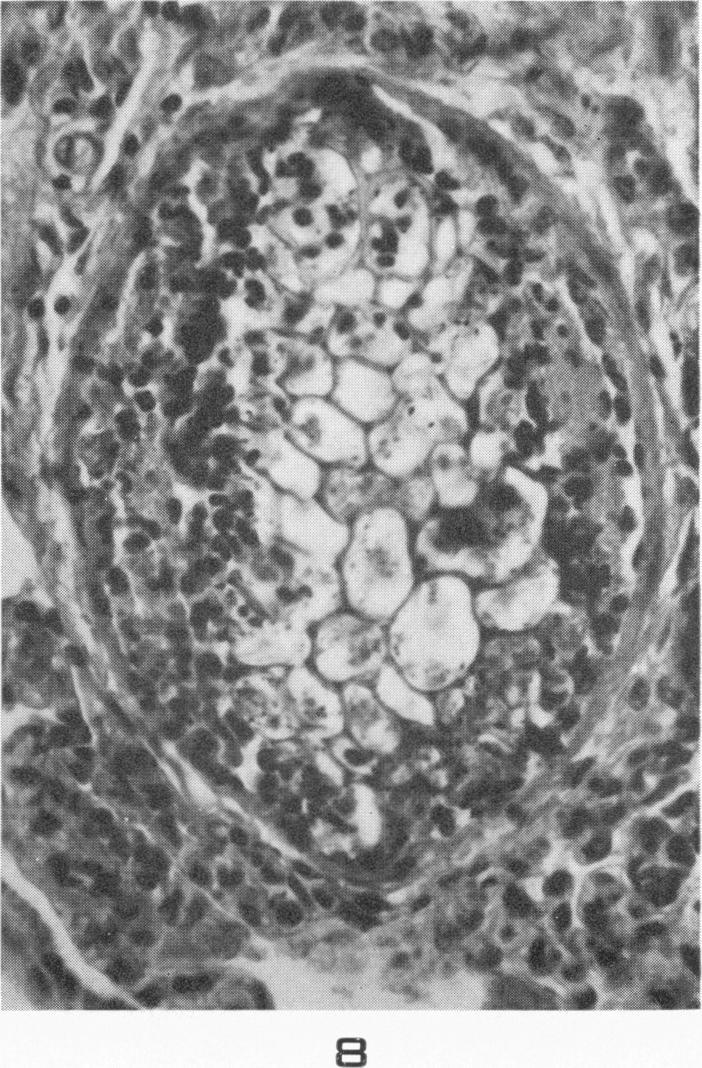

Chyme emboli in the lungs of goats wounded by missiles.

Am J Pathol. 1956 Jul-Aug;32(4):831-43.